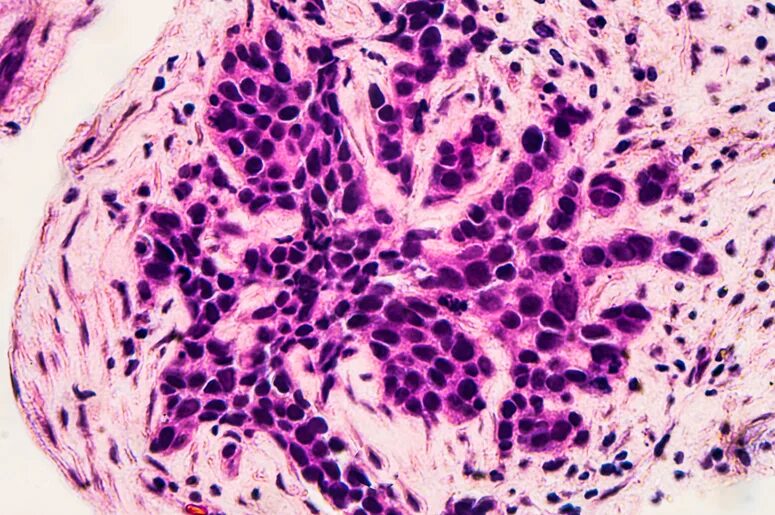

Протоковая карцинома молочной железы гистология. протоковая карцинома молочной железы микропрепарат. внутрипротоковая карцинома молочной железы гистология. внутрипротоковая карцинома молочной железы микропрепарат.

Внутрипротоковая карцинома молочной железы микропрепарат. внутрипротоковая карцинома молочной железы гистология. неинфильтрирующий внутрипротоковый карцинома. протоковая карцинома in situ молочной железы.

Внутрипротоковая карцинома. гистологическая классификация опухолей молочной железы. неинфильтрирующий внутрипротоковый карцинома.

Тубулярная карцинома гистология. протоковая карцинома in situ. внутрипротоковая карцинома молочной железы микропрепарат. карциномы in situ молочной железы гистология.

Протоковая карцинома in situ. опухоли молочной железы микропрепарат. протоковая карцинома молочной железы гистология. комедокарцинома гистология.

Инфильтрирующая карцинома молочной железы гистология. внутрипротоковая карцинома молочной железы микропрепарат. внутрипротоковая карцинома молочной железы гистология. комедокарцинома гистология.

Внутрипротоковая карцинома молочной железы гистология. внутрипротоковая карцинома молочной железы микропрепарат. инфильтрирующая карцинома молочной железы гистология. комедокарцинома гистология.

Протоковая карцинома молочной железы микропрепарат. протоковая карцинома молочной железы гистология. инфильтрирующая карцинома молочной железы гистология. карцинома молочной железы гистология.

Протоковая карцинома молочной железы g3. протоковая карцинома молочной железы микропрепарат. инвазивная карцинома молочной железы g3. инфильтрирующая карцинома молочной железы гистология.

Инфильтрирующая карцинома молочной железы гистология. протоковая карцинома молочной железы микропрепарат. инфильтрирующая протоковая карцинома молочной железы g2.

Инвазивная протоковая карцинома молочной железы g3. инвазивная протоковая карцинома микропрепарат. инфильтративный карцинома g2. протоковая карцинома молочной железы микропрепарат.

Инфильтрирующая протоковая карцинома g2. инфильтративная карцинома молочной железы неспецифического типа. инфильтрирующая карцинома неспецифического типа g1. инфильтрирующая протоковая карцинома молочной железы g2.